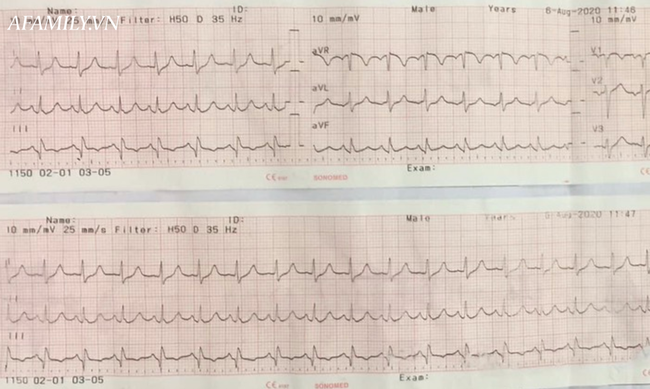

Điện tâm đồ ban đầu ghi nhận nhịp nhanh xoang phù hợp với chẩn đoán.

Hình ảnh điện tâm đồ của bệnh nhân.

Bất thường ở thất phải trên điện tâm đồ và siêu âm tim.